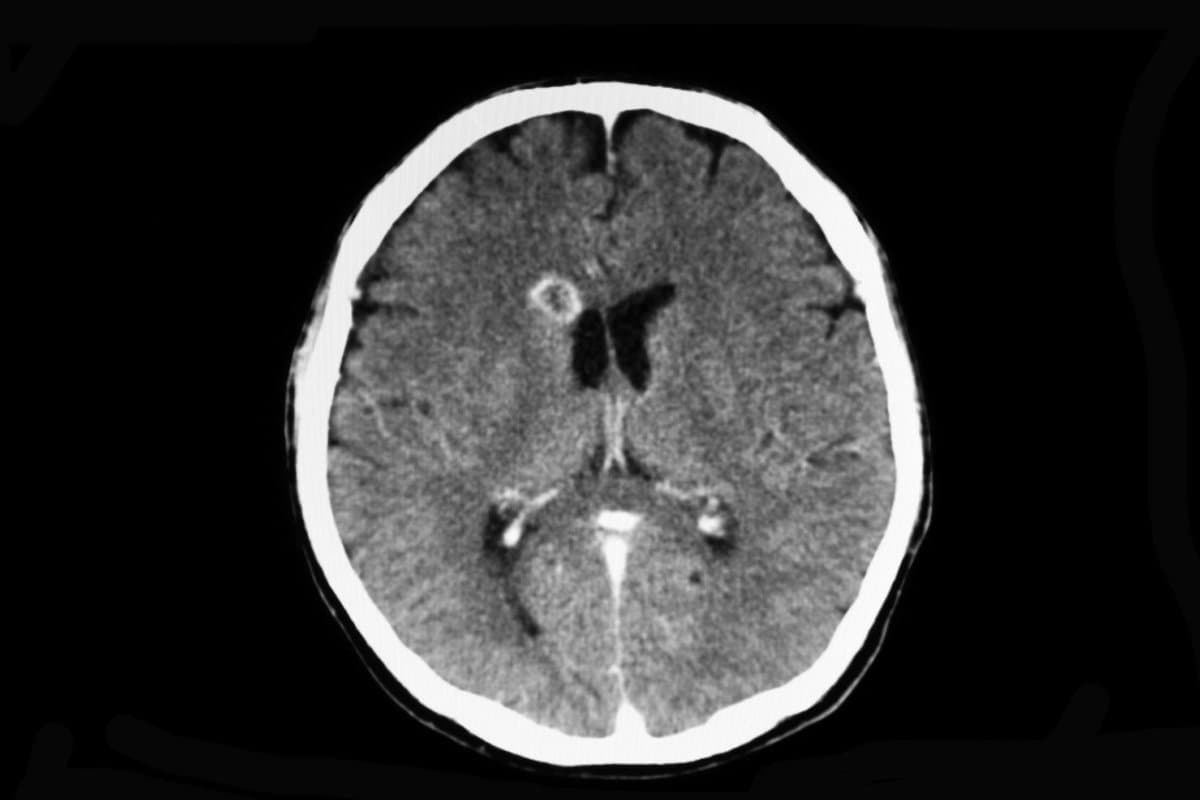

Hirnabszesse erkennen und behandeln

Der Hirnabszess ist eine seltene und lebensbedrohliche Erkrankung, die durch eine Vielzahl unterschiedlicher Erreger verursacht werden und auch immunkompetente Personen betreffen kann. In der Behandlung von Hirnabszessen sind sowohl medikamentöse Maßnahmen als auch die Neurochirurgie gefragt. Bei korrekter Diagnose und Therapie ist die Prognose mittlerweile gut. Eine neue Leitlinie der ESCMID fasst den Evidenzstand zu Diagnostik und Therapie zusammen.

Studien im Tiermodell zeigen, dass die Entwicklung eines Hirnabszesses über die ersten drei Tage durch frühe Cerebritis und bakterielles Wachstum charakterisiert ist. In den folgenden Tagen kommt es zur späten Cerebritis mit Ausbildung einer zentralen Nekrose und zur Einwanderung von Makrophagen und Fibroblasten in die Peripherie des Abszesses. Ab dem zehnten Tag nimmt die Nekrose ab und es bildet sich eine Kollagenkapsel, die etwa um Tag 14 den Abszess komplett umschließt.